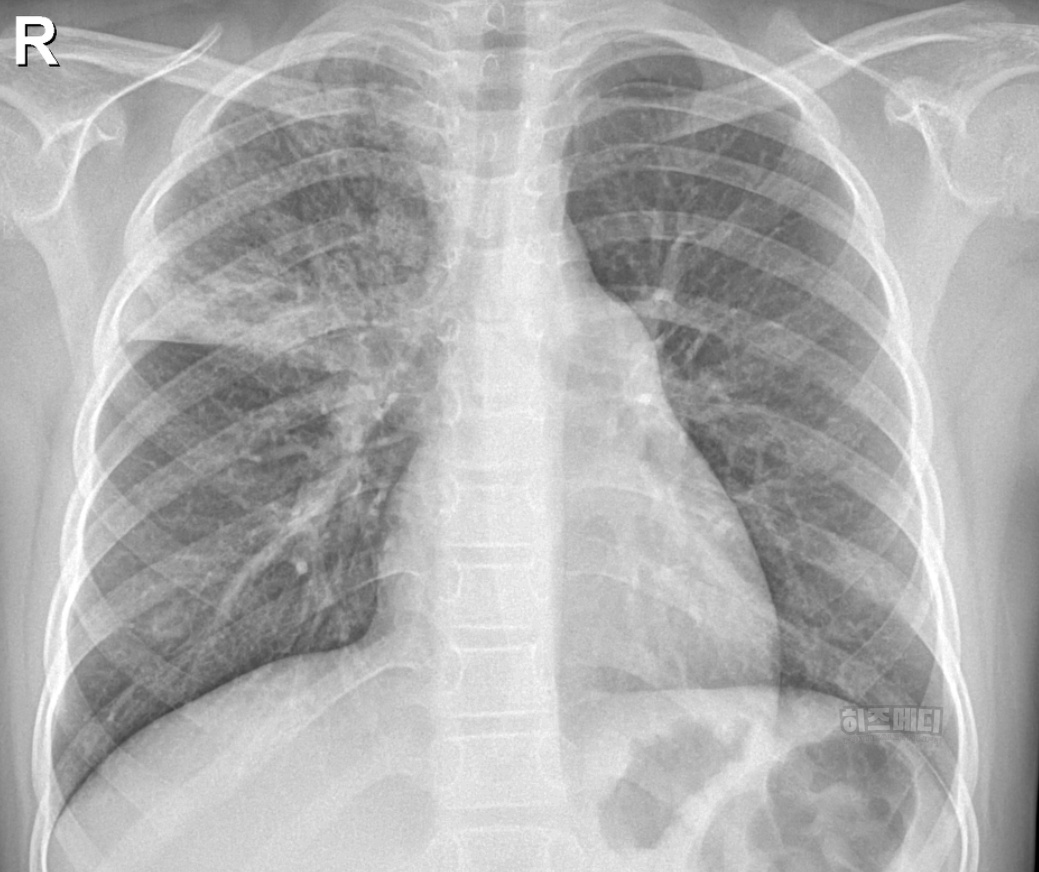

1) 흉부 엑스레이 촬영

폐에 염증이 있는지 확인할 때 흉부 엑스레이를 시행할 수 있습니다. 보통 폐렴으로 발전한 경우, 흉부 엑스레이에서 폐에 하얀 음영이 나타납니다.

마이코플라스마 폐렴은 일반적으로 폐렴의 전형적인 엑스레이 소견과는 다를 때가 많습니다. 폐의 폐포와 혈관사이를 간질이라고 부르는데, 이 부분에 주로 하얀 음영들이 많이 보이게 됩니다.

또한 병변이 양쪽 폐에서 동시에 관찰되는 경우가 종종 나타나며 주로 폐의 하엽에 많이 나타납니다. 미세한 결절이나 그물망 같은 모습으로 나타나기도 합니다.

마이코플라스마 폐렴은 엑스레이 사진에서는 병변이 심하지 않은데도 증상을 심하게 호소하는 경우가 있으며, 반대로 엑스레이 소견은 심해 보이는데 증상은 경미한 경우도 흔합니다. 따라서 마이코플라스마 감염을 확진하기 위해서는 임상 증상과 혈액검사 등의 종합적인 평가가 필요합니다.